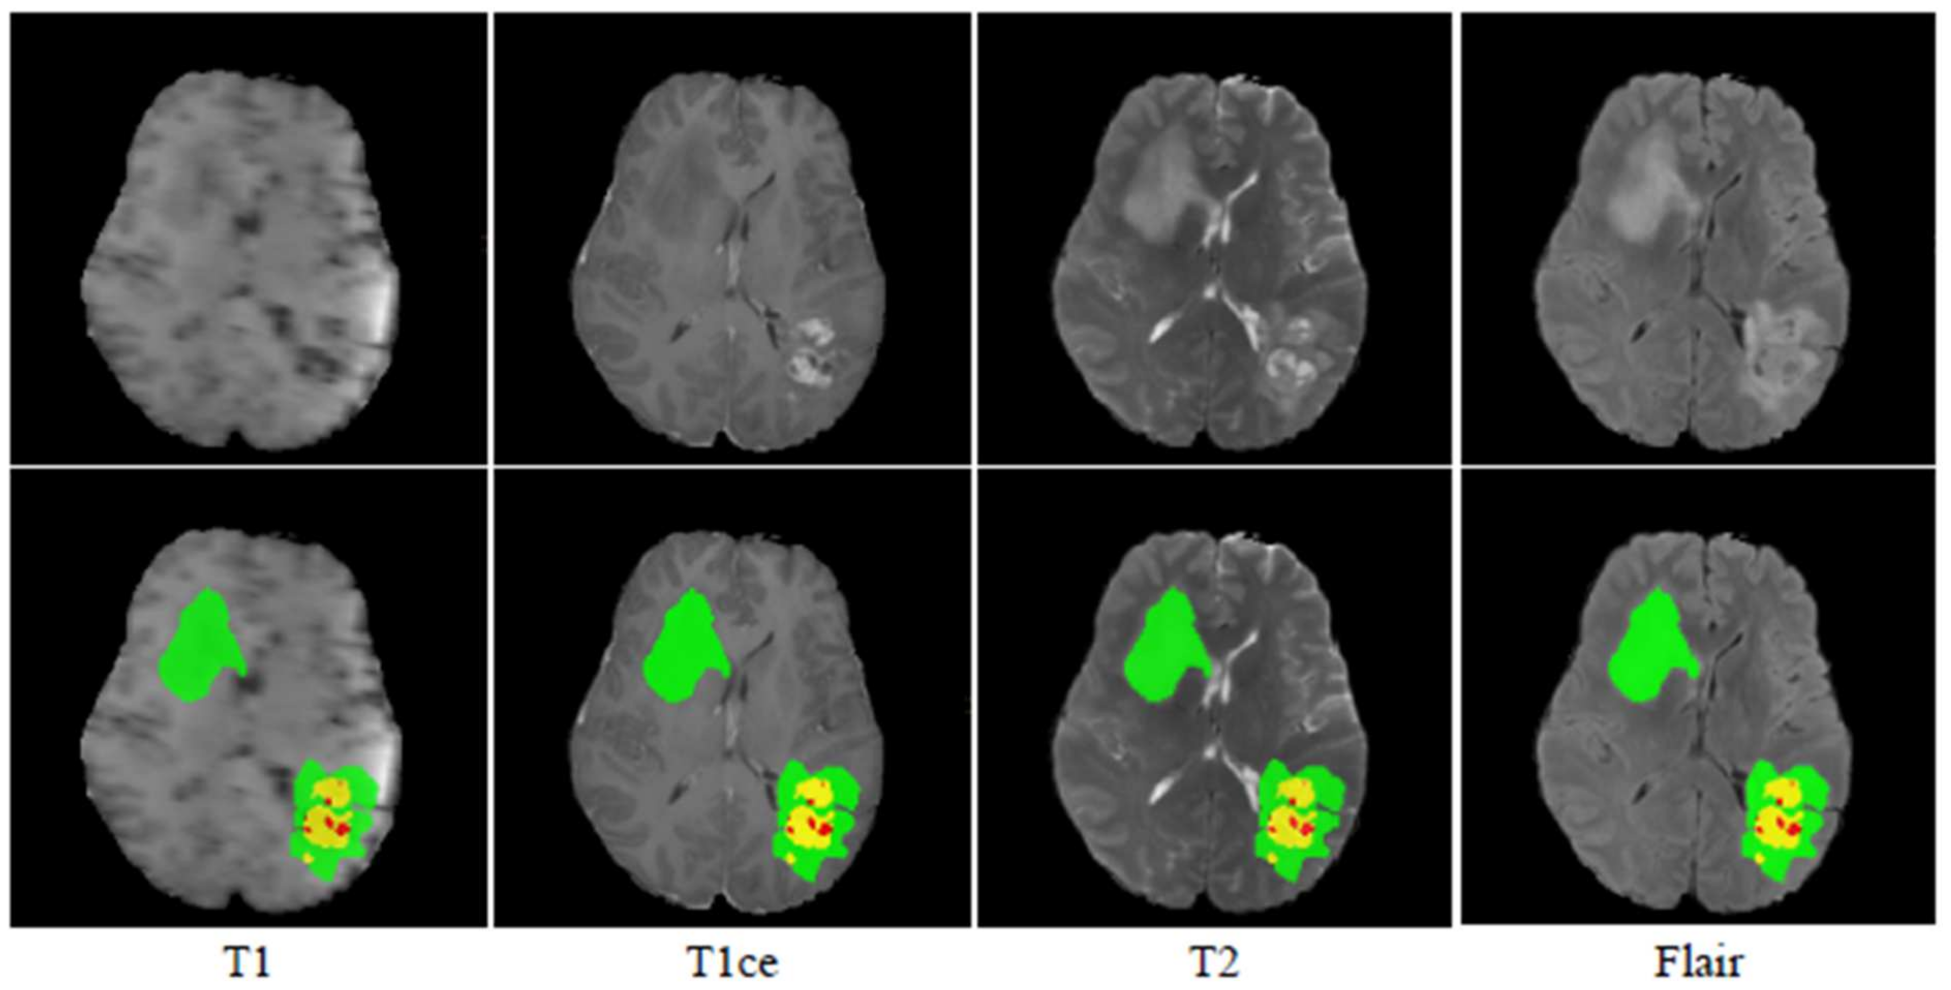

The BraTS 2018 challenge training dataset [22,23,24] consists of 210 HGG and 75 LGG scans. The validation dataset includes 66 different MRI scans. All MRI of the BraTS 2018 dataset has a volume dimension of 240 × 240 × 155. The MRI volumes have been segmented manually by one to four raters, and experienced neuroradiologists approved their annotations. Each tumor was segmented into edema, necrosis, and non-enhancing tumor and active/enhancing tumor. The sample images from the BraTS 2018 dataset are shown in Figure 6.

Figure 6. MRI images and their ground truth for various modalities. Green, red, and blue highlight the ED, NET, and ET areas, respectively.